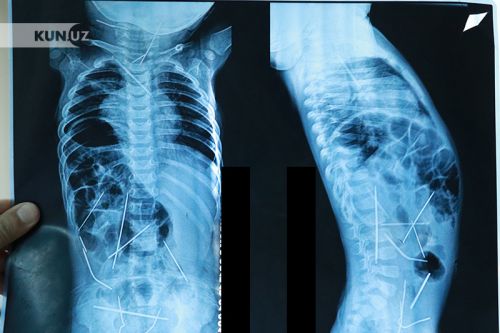

Рентгеновские снимки показали, что у ребенка были 16 игл в теле, и они причиняли ему боль в течение, как минимум, двух месяцев. Таким образом, мальчик и его мать немедленно были отправлены в Ташкент. В Республиканском центре скорой медицинской помощи ему была сделана операция.

По словам руководителя Центра детской хирургии, профессора Хабибуллы Акилова, все иглы были в различных местах: их обнаружили в толстом кишечнике, мочевом пузыре, внутри грудной клетки, шее, позвоночнике и под сердцем.